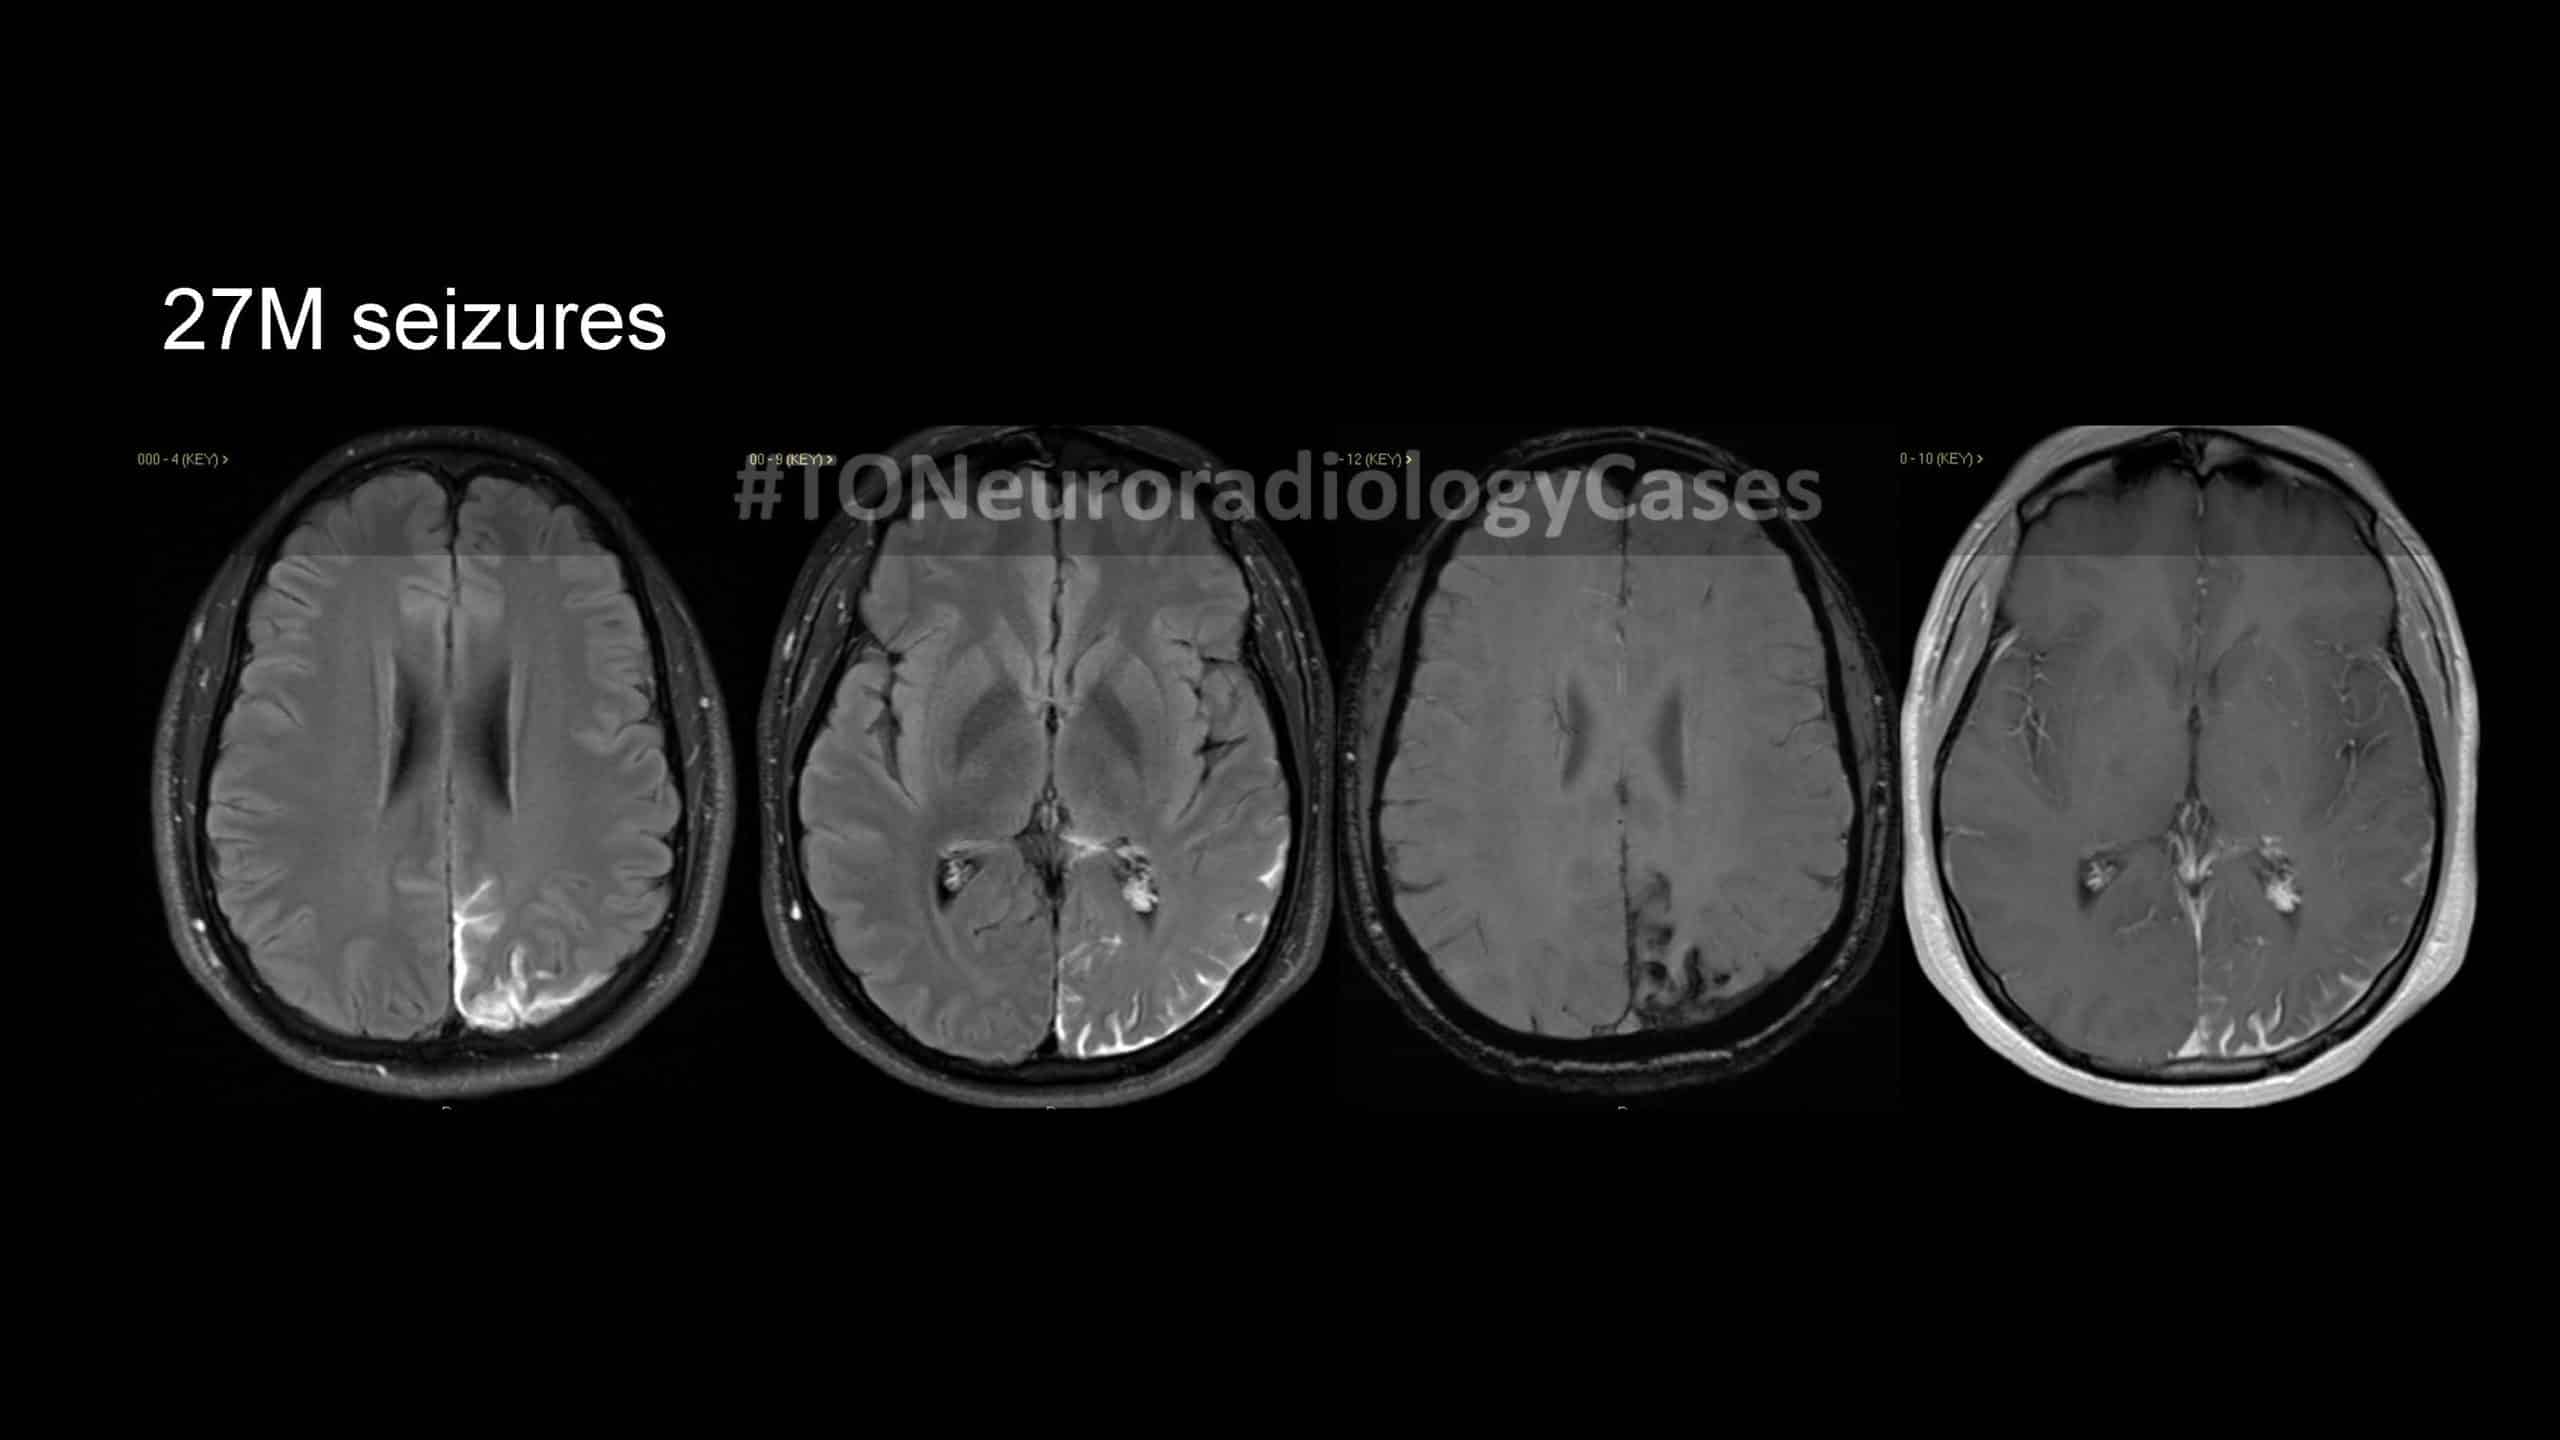

DR. AMY CHEN’S

Neuroradiology Case of the Week

@ Toronto Radiology

Over the past few years, I’ve had the pleasure of curating a “Case of the Week” contest with contributions from radiologists across the city, designed to challenge and engage our neuroradiology fellows at the University of Toronto. This collection showcases a range of neuroradiology cases from our city and have been a fun part of our fellow’s educational experience. I am excited to share this resource with a wider audience, now featured on our Toronto Radiology departmental website.

New cases will be added periodically, so be sure to check back for the latest updates!